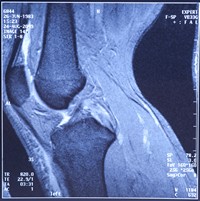

The technology used by ADVANCED TELEMEDICINE SOLUTIONS is focused on enabling radiologists and specialists from

other areas to get precise, trustworthy exam results in real time, from any approved location. Exam results include

conventional X-Rays, tomography, magnetic resonances, mammograms and ultrasounds, among others.